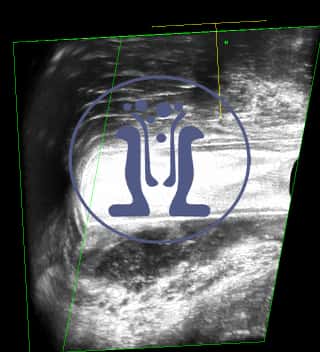

Τα αποστήματα και στους οι δυο ασθενείς προκλήθηκαν από περιεδρικά συρίγγια. Και οι δύο προγραμματίζονται για διάνοιξη του συριγγίου και λυσιτελή θεραπεία.